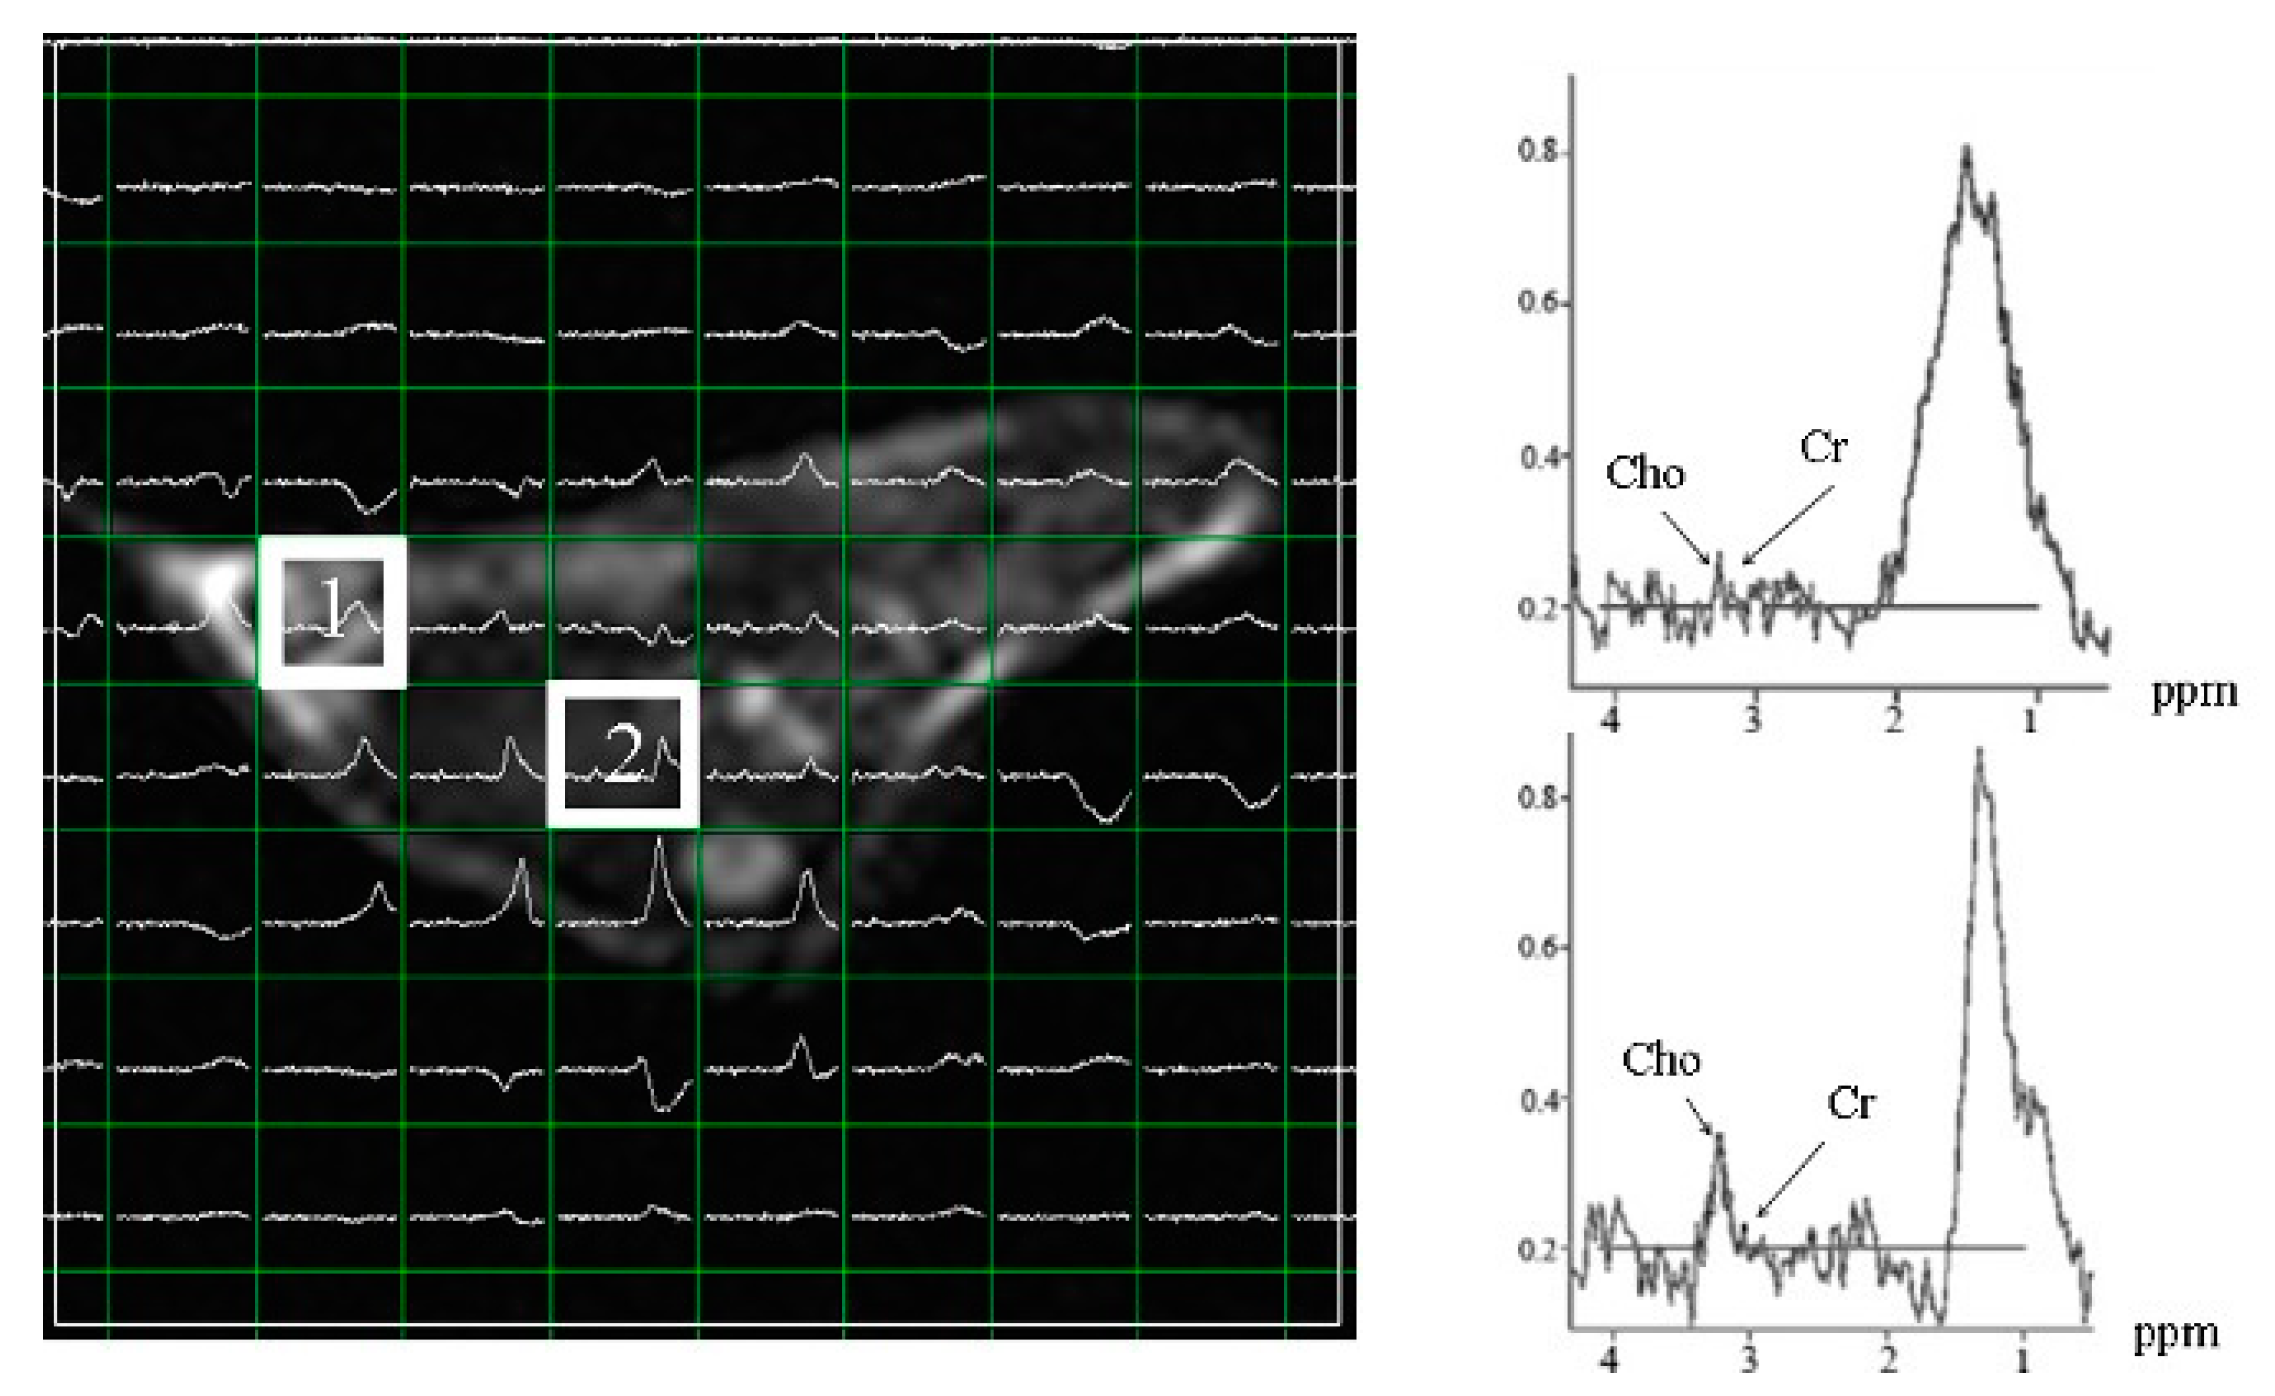

Next, in vivo effects of tagitinin C were evaluated using MRS. The control and experimental groups showed variable degrees of anaplasia, increased mitotic and metastatic activity, and irregular masses on macroscopic examination. As revealed by the MR assay, tumor cells spread throughout the abdomen and metastasized to several organs in the xenografted mice. Since evaluation of the significantly reduced hepatoma mass compared to that in the control mice was not possible (Figure 5), we acquired the multi-voxel spectra of the hepatoma after 25 days of inoculation with Hep-G2 cells. Based on the MRS of voxel 1, Hep-G2 inoculated voxel 1 had low choline levels (shown in the MRS of voxel 1). Voxel 2 had the highest levels of choline in the same cross-section. Hep-G2 cells migrated from voxel 1 to voxel 2, as indicated by high choline levels. Creatine was used as an internal standard.

Figure 5.

Multi-voxel spectra of hepatoma in subcutaneous Hep-G2-xenografted mice after 25 days of inoculation. Voxel 1 shows the inoculation point of Hep-G2. Voxel 2 shows the maximum choline levels, indicating that Hep-G2 cells migrated from voxel 1 to voxel 2. Cho: choline; Cr: creatine.